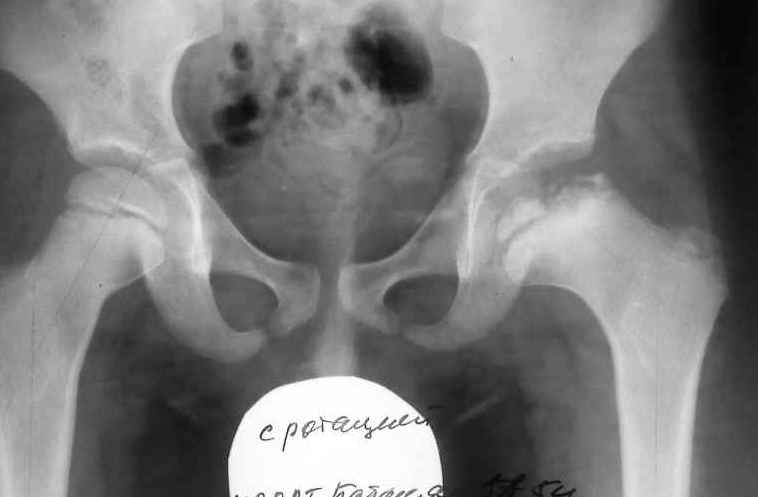

Ребёнок 5 лет заболел в июне текущего года , когда появились боли в области левого коленного

сустава. Обратились за помощью к кардио-ревматологу по месту жительства. Получал

консервативное лечение по поводу артрита левого коленного сустава. В июле осмотрен

ортопедом , поставлен диагноз остеохондропатия головки левого бедра - болезнь Пертеса 4-5

ст .Rg- картина представлена . Уважаемые коллеги ! Дайте совет , какой способ лечения

необходим данному пациенту. Есть мысль- выполнить подвертельную деторсионно

медиализирующую остеотомию проксимального отдела бедра.